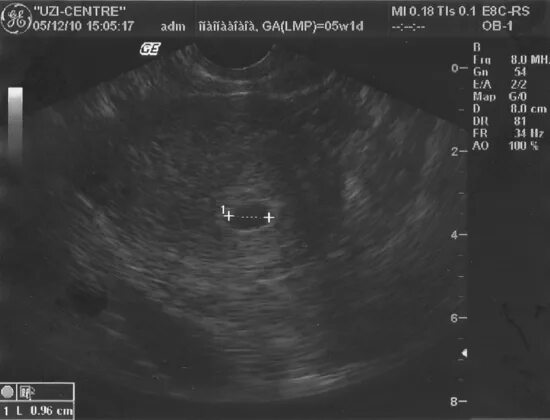

Первая неделя беременности признаки и ощущения